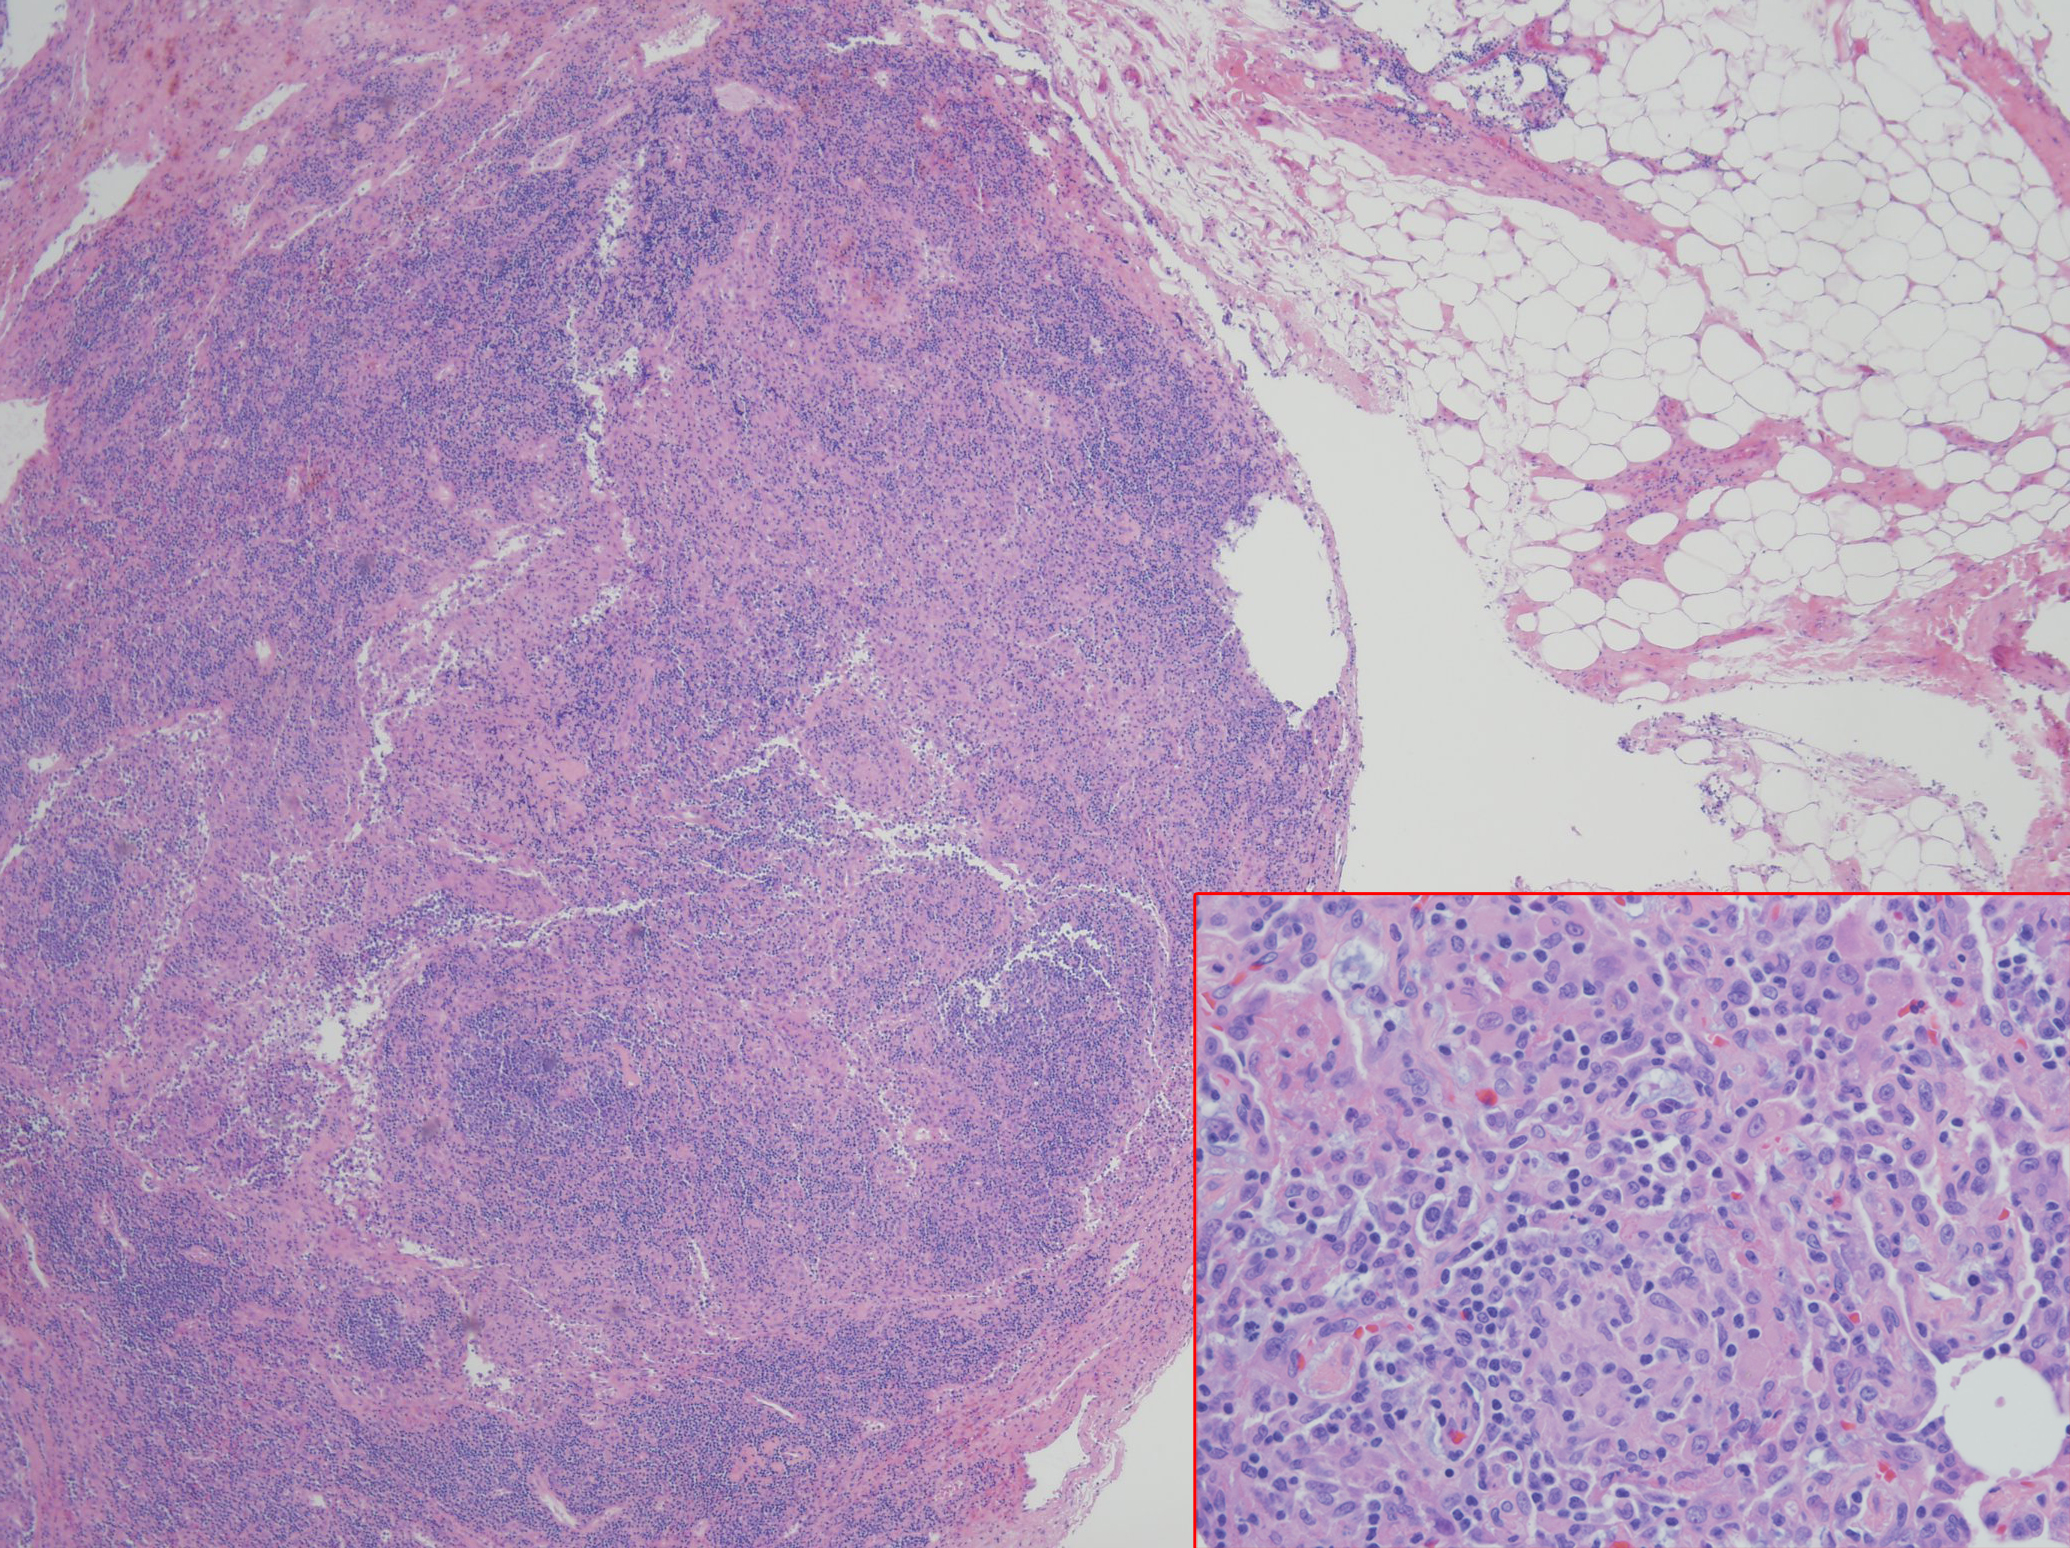

Case Presentation: A 34 year old male with a history of CVID subclass 2 and 4, with low IgG level, absent IgA, liver nodular regenerative hyperplasia with portal hypertension, and immune thrombocytopenic purpura status post splenectomy presented with a month of nonproductive cough, mild episodes of hemoptysis, and shortness of breath. Physical exam revealed peripheral capillary oxygen saturation of 89% at rest and 85% with ambulation, multiple petechiae on upper chest and bilateral shoulders, spider angiomata, clubbing, and cyanosis on all upper extremity digits. Laboratory studies were notable for eosinophilia with lymphocytosis, alkaline phostphatase 266 U/L, Total bilirubin 3.6 mg/dL, Direct bilirubin 1.3 mg/dL, Indirect bilirubin 2.3 mg/dL, BNP 160 pg/mL, Tryptase 19.6 µg/L, negative Influenza and ANCA. Chest x-ray showed small lung volumes. Chest CT angiogram showed no pulmonary emboli, mild right upper lobe tree-in-bud opacities; diffuse lymphadenopathy without changes from CT done at diagnosis of CVID. Pulmonary function test was normal. Transthoracic echocardiogram revealed an ejection fraction (EF) of 56-60% with an interatrial shunt and a mildly dilated left ventricle. Cardiac catheterization demonstrated a small patent foramen ovale (PFO) with right-to-left shunt, which was also demonstrated on V/Q scan. Bone marrow biopsy showed no evidence of malignancy. Bronchoscopy cultures revealed no infectious etiology. Given results above, hypoxemia was attributed to a combination of PFO and chronic lymphangitic changes with enlarging lymphadenopathy, unable to rule out lymphoma. Lymph node biopsy did not yield diagnostic result. Therefore, left video-assisted thoracoscopy with biopsy demonstrated non-necrotizing interstitial granulomas and follicular lumphoid hyperplasia. This finding was diagnostic for GLILD, a rare pulmonary disease that explained the patient’s hypoxemia. He improved significantly with rituximab followed by azathioprine, and intravenous immunoglobulin (IVIG).

Discussion: CVID is a lifelong primary immunodeficiency disorder characterized by impaired B-cell differentiation, low immunoglobulin levels, recurrent bacterial infections and malignant disorders involving lung, gastrointestinal tract, liver, and spleen. Approximately 20% of CVID is complicated by granulamatous-lymphocytic interstitial lung disease (GLILD), which is a diffuse lung parenchymal disease characterized by non-necrotizing granulomas, lymphoid interstitial pneumonia, and follicular bronchiolitis on histopathology. GLILD is associated with significant morbidity and mortality and its etiology is unknown. Common initial presentation includes dyspnea but may be asymptomatic. GLILD can be challenging to distinguish from sarcoidosis and lymphoma. Diagnosis requires a surgical lung biopsy. Optimal therapies that follow the diagnosis are unknown, although prednisone and IVIG are considered to be the first line therapy in GLILD, especially those with lymphoproliferative disease. Therapy with a combination of rituximab and azathioprine was successfully in some cases.